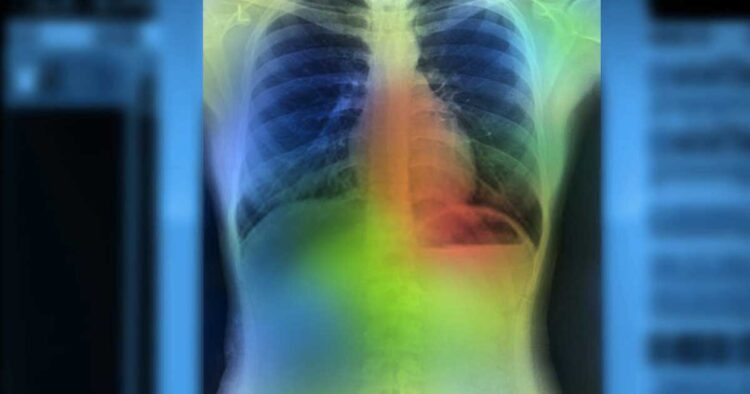

- To deal with this, Facebook AI has currently added pre-educated device studying (ML) fashions to assist docs to task the analysis of COVID sufferers to make powerful medical choices and allocate resources. The study is part of an ongoing collaboration with NYU Langone Health’s Predictive Analytics Unit and Department of Radiology. The ML fashions are used to expect affected person deterioration using X-ray Radiographs.

- The test proved the ML version could expect the deterioration of COVID-19 sufferers as much as ninety-six hours with the best accuracy. The researchers accept as accurate with an understanding like this could help healthcare companies expect the call for the sources that might be essential to cope with high-danger Tech Explained Deep mastering techniques for image-primarily based analysis use supervised schooling widespread in predicting the danger of decay in COVID-19 patients. However, such methods include numerous constraints, just like labeled information, pricey education, etc.

- Self-supervised education achieves better overall performance accuracy for predicting an unfavorable occasion in any respect of time points. According to the paper, the group used the NYU COVID-19 dataset with over 26 thousand X-ray radiographs from 4,914 sufferers for tuning the model. The labeled facts confirmed whether the patient’s situation deteriorated inside ninety-six hours of the scan,